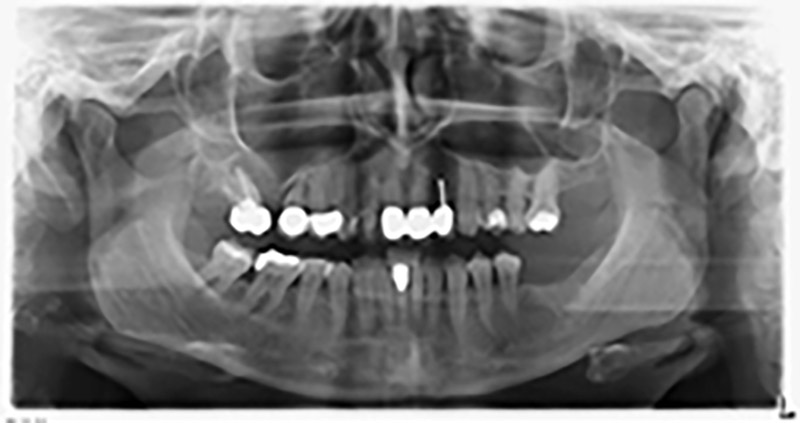

Orthopantomogram

Image 20: Orthopantomogram after treatment